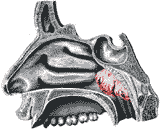

На рисунке красным цветом показано место расположения аденоидных вегетаций в носоглотке.

Расположение аденоидных вегетаций в носоглотке.(аденоидные вегетации выделены красным цветом)